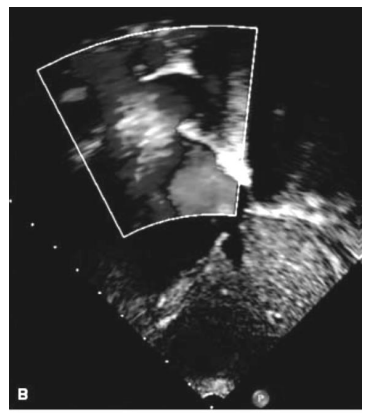

Paciente de 2 anos é levado para avaliação cardiológica após realização de ecocardiograma por sopro cardíaco. Os pais negam sintomas na criança. A respeito da patologia ilustrada no resultado do exame, assinale a alternativa correta.

Paciente de 2 anos é levado para avaliação cardiológica após realização de ecocardiograma por sopro cardíaco. Os pais negam sintomas na criança. A respeito da patologia ilustrada no resultado do exame, assinale a alternativa correta.